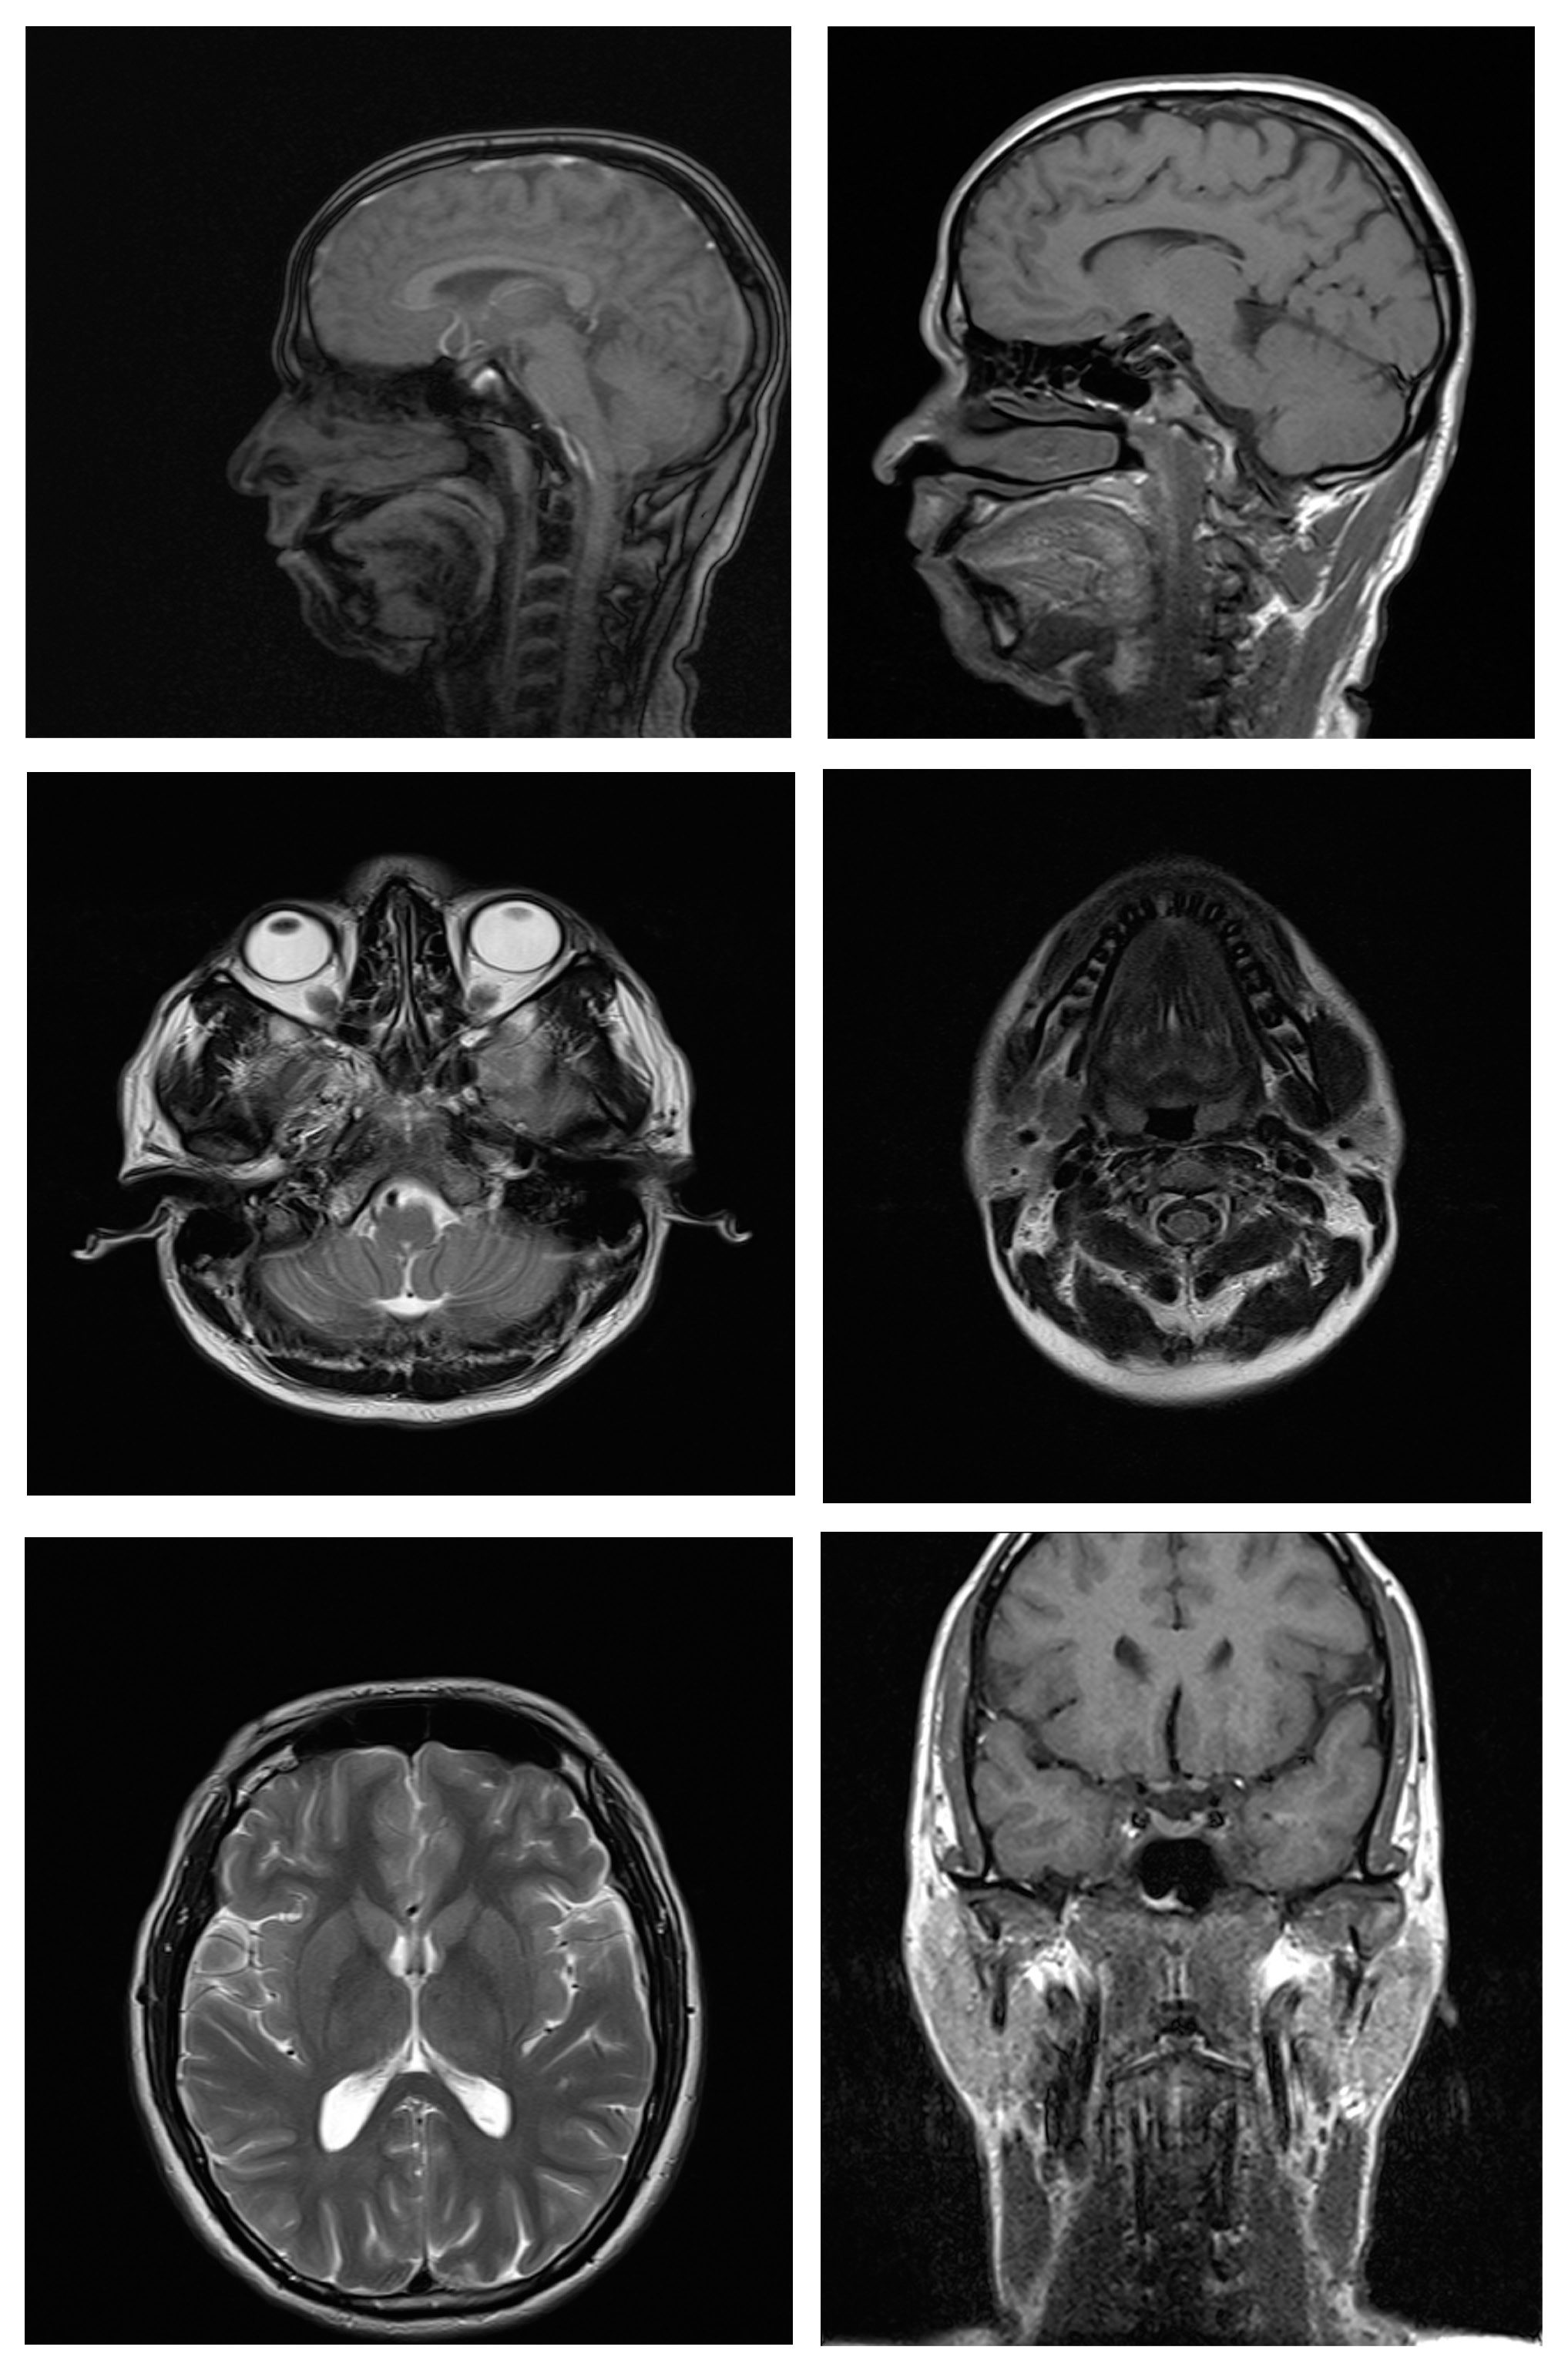

Magnetic resonance imaging scans were taken for all 38 subjects to study diagnostic image quality. Since the orthodontic appliances were securely bonded with orthodontic composite, there were no special precautions taken regarding the possible dislodgement and heating of the appliances, as previous studies had found changes in the temperature of the appliances to be clinically insignificant (within 1°C).16 The MRI scans for all types of bracket and retainer materials are shown in Figure 1, Figure 2, Figure 3, Figure 4, Figure 5, Figure 6, Figure 7, Figure 8, Figure 9, Figure 10. Non-diagnostic or unclear ROI are marked with arrows. None of the patients reported any discomfort or pain during MRI examination. The MRI scans were analyzed by a panel of 6 qualified and licensed radiologists, who assessed their diagnostic quality. The scans were compared with controls that included images from the archives of the Department of Radio-Diagnosis of Kamineni Institute of Medical Sciences. The radiologists ranked the images according to the distortion observed in the abovementioned ROI, using the modified receiver operating characteristic (ROC) analysis of distortion scoring system (Table 2), as described by Elison et al.17 In this method of distortion classification, a score of 3 represents the cut-off point for clinical usability. Images with a score of 3 have moderate distortion or artifacts, but they can still be used for diagnosis.

Sometimes, a combination of different fixed retainers is placed in the maxillary and mandibular arches based on the orthodontist’s choice, the availability of retainers or the patient’s preference. Hence, combinations of fixed retainers placed in the maxillary and mandibular arches were also examined in this study, as they have not been studied until now.

The combination of a stainless steel retainer in the maxillary arch and a fiber-reinforced retainer in the mandibular arch had a mean distortion score of 2.00 and mean distortion scores of 2.00 for TMJ, the tongue, the maxilla, the mandible, and the maxillary sinus; the posterior cerebral fossa had a score of 1.00. Therefore, the MR images with this combination caused minimal or no distortion, and were considered diagnostic by the radiologists.

The combination of a stainless steel retainer in the maxillary arch and a titanium retainer in the mandibular arch received similar scores to the previous combination. Therefore, the MR images with a stainless steel retainer in the maxillary arch and a titanium retainer in the mandibular arch were considered diagnostic.